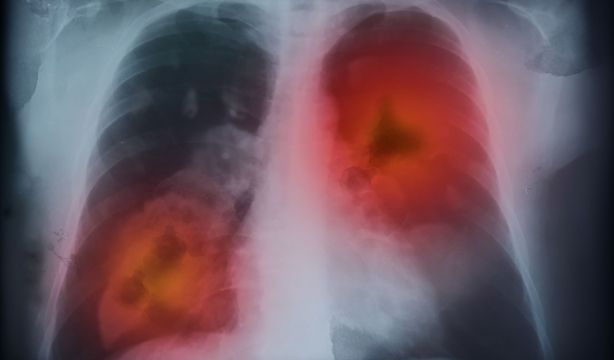

Un biomarcador permite saber si un tratamiento de cáncer de pulmón funciona

Investigadores españoles han identificado un biomarcador no invasivo para predecir el beneficio clínico duradero de la inmunoterapia, basado en la integración de datos radiómicos y clínicos monitorizados, durante los primeros meses de tratamiento con anticuerpos monoclonales anti-PD-1/PD-L1, en pacientes con cáncer de pulmón no microcítico avanzado.

La inmunoterapia se ha convertido en uno de los tratamientos de referencia del cáncer de pulmón avanzado no microcítico, con tasas de respuesta prometedoras, enfermedad que sigue presentándose con una frecuencia alta. La predicción de la eficacia de la respuesta al tratamiento, antes y durante el tratamiento, sigue siendo crítica para el manejo personalizado de los pacientes.